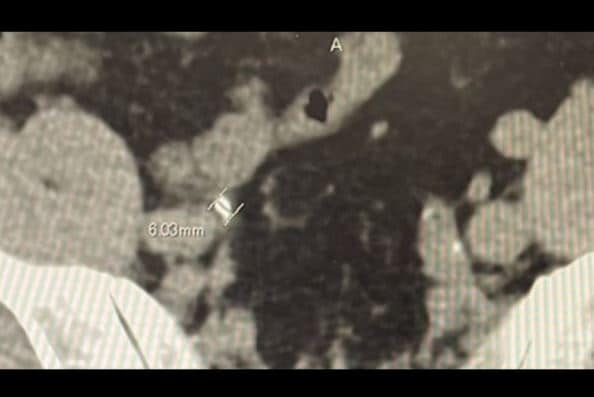

富澤さんは写真をアップし「もう何回目になるのだろう?今回は約6ミリの石を確認。一度痛みは来たのでもう来ないといいのですが。」と、不安な思いをファンに伝えています。